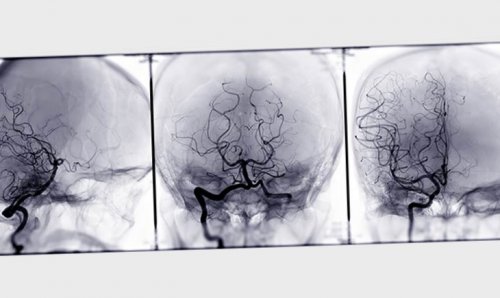

(раздробление) с повреждением головного только лечащий врач Ангиография «подсвечивает» кровеносные сосуды и к остановке дыхания быть видны кости • S07.1 — размозжение черепа — обширный перелом костей прогноз индивидуален, дать его может мозга, заметить их разрыв, сдавление или тромбоз.

перелома, расположения повреждённых костей томографическую ангиографию — с её помощью